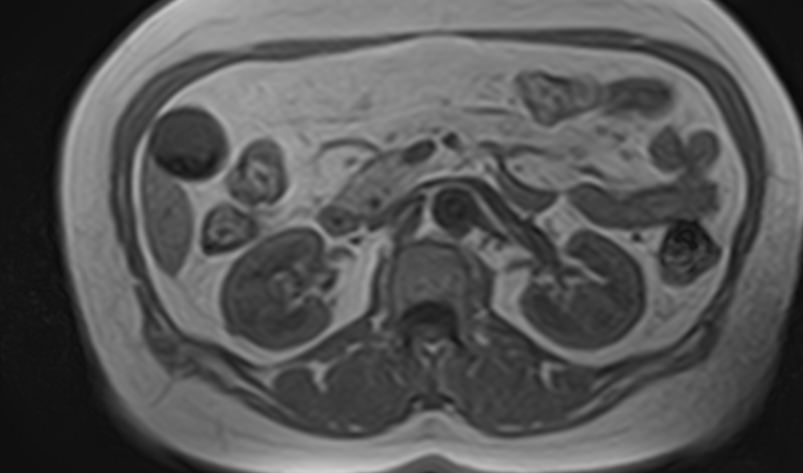

Мочеточники — это парные трубчатые органы, длиной приблизительно 25-30 см, соединяющие почечные лоханки с мочевым пузырем. Наиболее частой патологией является нарушение оттока мочи по мочеточнику за счет сужения (стриктуры) или обтурации (полной закупорки) его просвета.

Магнитно-резонансная томография позволяет получить информацию о состоянии мочеточников и окружающих мягких тканей для точной диагностики заболеваний данной анатомической области.

При подозрении на опухолевый процесс в обязательном порядке проводится контрастное усиление. Для этого внутривенно вводится контрастное вещество, которое фиксируется в патологических очагах, что отображается в виде более яркого свечения по сравнению с окружающими тканями. С помощью контрастирования возможно выявить опухолевые процессы на ранних стадиях развития, что значительно повышает шансы на успешное лечение и выздоровление.

В первую очередь необходимо отметить, что магнитно-резонансная томография мочеточников выполняется в комплексном обследовании почек и мочевыводящих путей, как самостоятельный метод диагностирования невозможен.

При помощи магнитно-резонансной томографии удается оценить состояние органов и выявить имеющиеся патологии:

- выявить патологические очаги и имеющиеся зоны поражения в мочеточниках;

- определить наличие новообразований, его размеры;